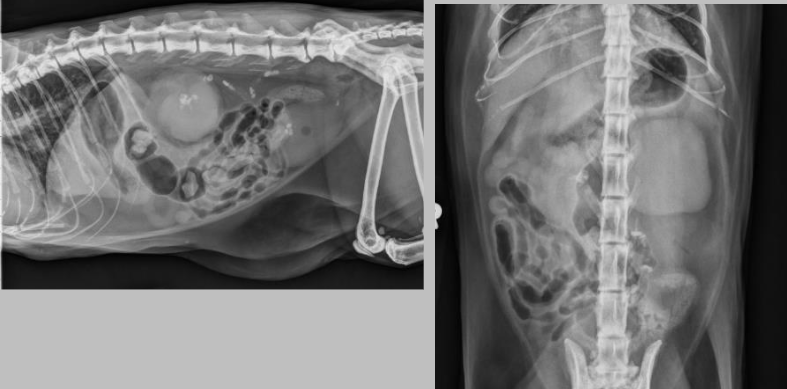

what is going on here bruh??

there is a mineralized adrenal mass. on the VD the mass is seen just left to the spine, and on the lateral, you can see a crescent shape opacity adjacent to the left kidney.